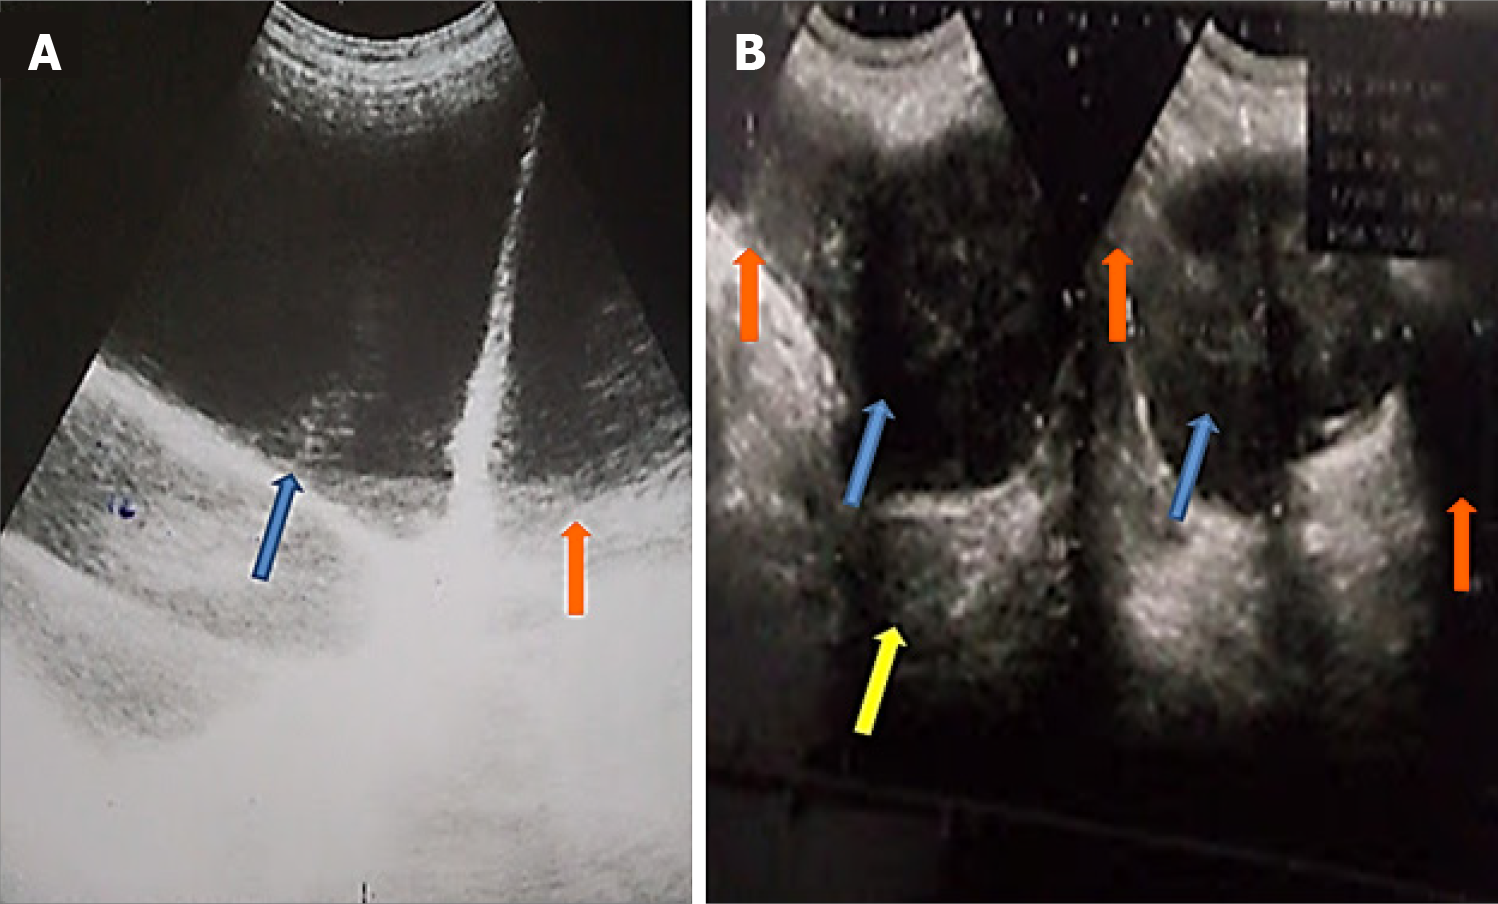

Figure 1 Transabdominal ultrasound scan.

A: Initial presentation of a patient with chronic urinary retention caused by benign prostatic hyperplasia and bladder diverticula (orange arrow), which are indistinguishable from the dilated bladder (blue arrow); B: Repeat ultrasound scan of the same patient after urethral catheterization, showing the right and left-sided bladder diverticula (orange arrows), bladder (blue arrows), and prostate (yellow arrow).